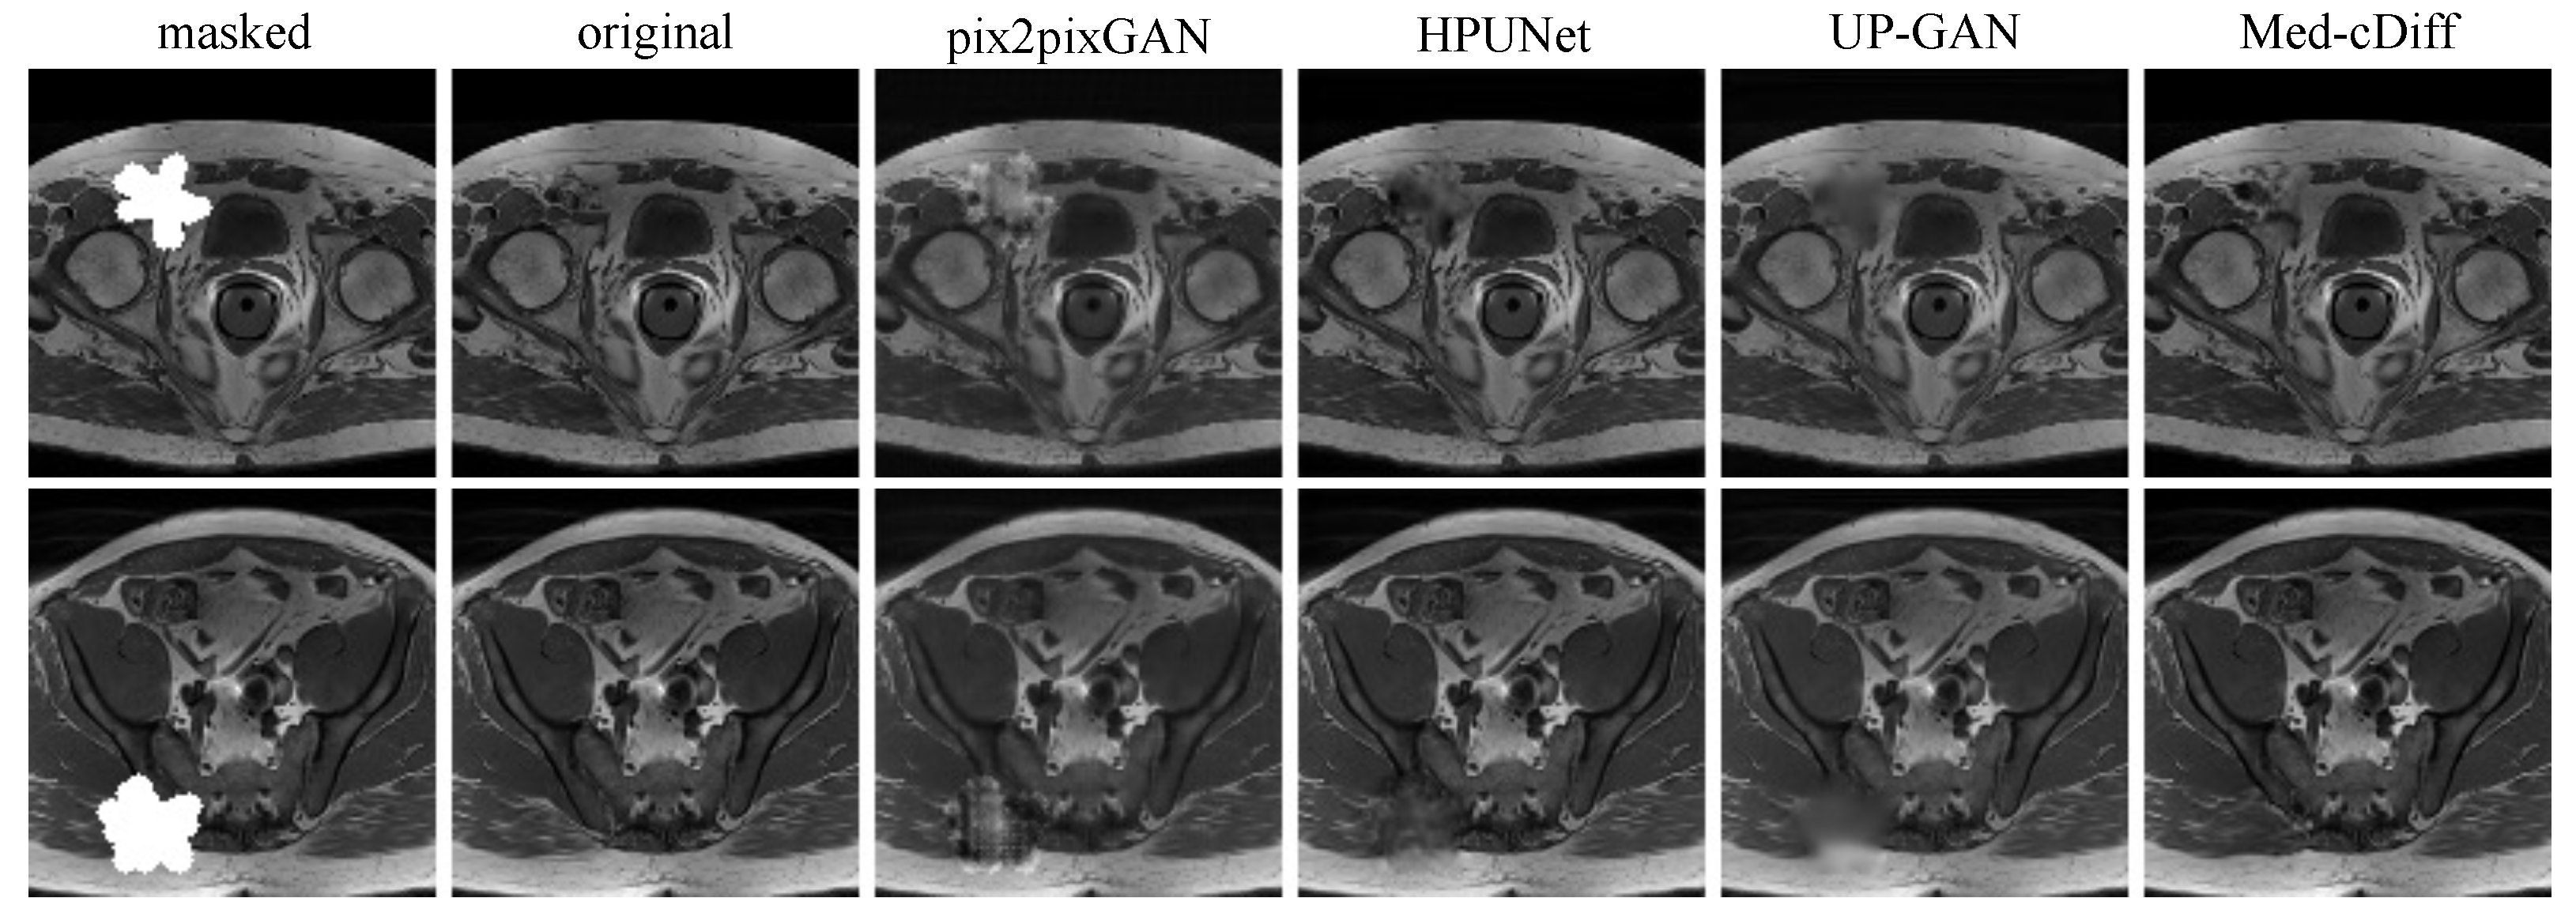

- MRI Inpainting: The dataset consists of 18,813 T1-weighted prostate MRI images that were acquired by the Spoiled Gradient Echo (SPGR) sequence. We used 6271 of them for testing. The masks were randomly generated during training, and they were fixed among different tests for testing.

4.5. MRI Inpainting

| LPIPS ()↓ | FID↓ | 2AFC Accuracy (%)↓ | |

|---|---|---|---|

| pix2pixGAN | 7.62 | 1.010 | 98.0 |

| HPUNet | 5.39 | 0.995 | 95.0 |

| UP-GAN | 3.17 | 0.897 | 94.5 |

| Med-cDiff | 2.96 | 0.582 | 64.0 |